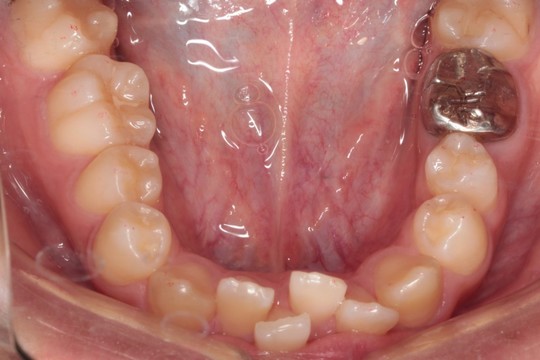

下顎 治療前

下顎 治療後

調布市の20代男性

主訴:前歯のデコボコを直したい

使用装置:インビザライン

治療期間:約2年

治療費用:93.5万円(税込)

治療結果:叢生が改善されました